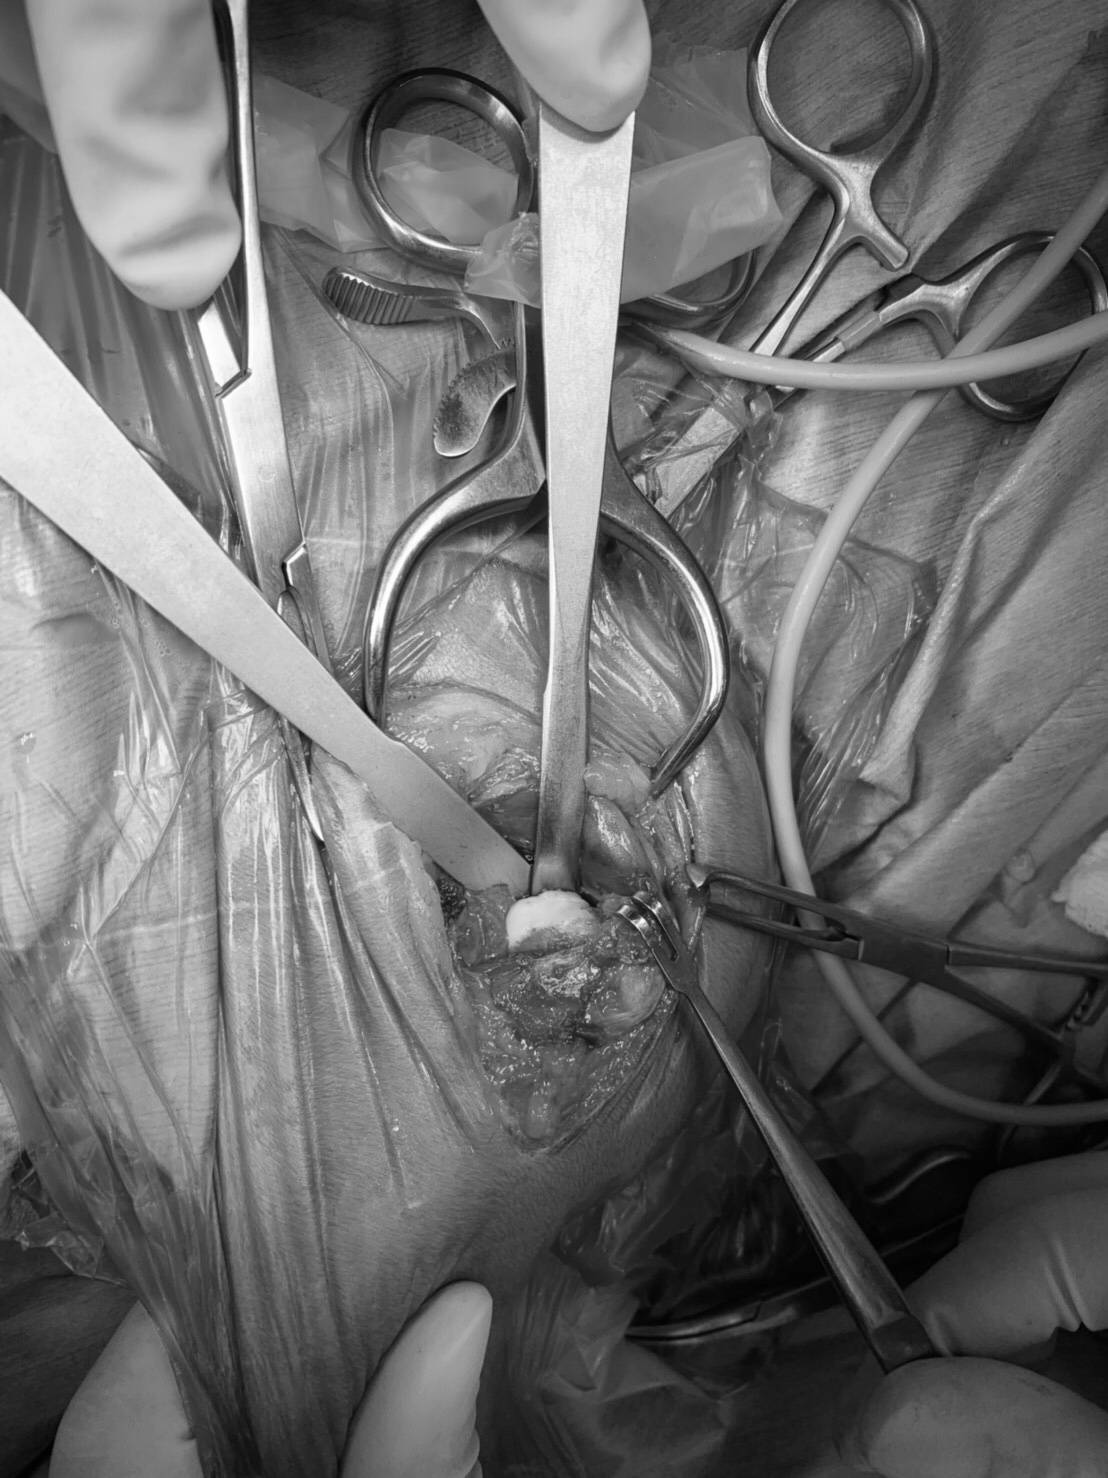

術中、骨頭・骨頚部切除前

術中、骨頭・骨頚部切除後。Cアームという特殊なX線装置を使い、切除ラインが適切かどうかを確認します

切除後の骨頭部。本来は滑らかな球形ですが、表面がボロボロになり剥離してしまっているのが分かります